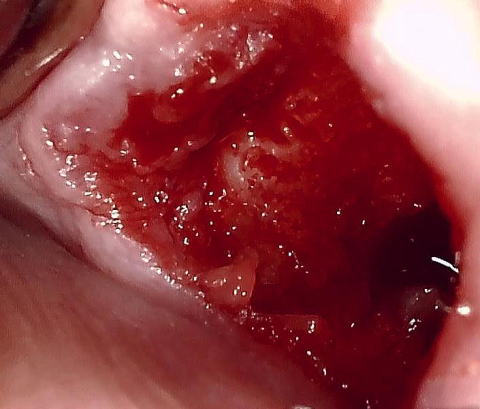

(図4)右上8埋伏抜歯後の翌日。筆者のDiathermyを用いた抜歯手術では、翌日にすでに肉芽で完全に覆われている。筆者は35年間Dry socketを発症させたことがない